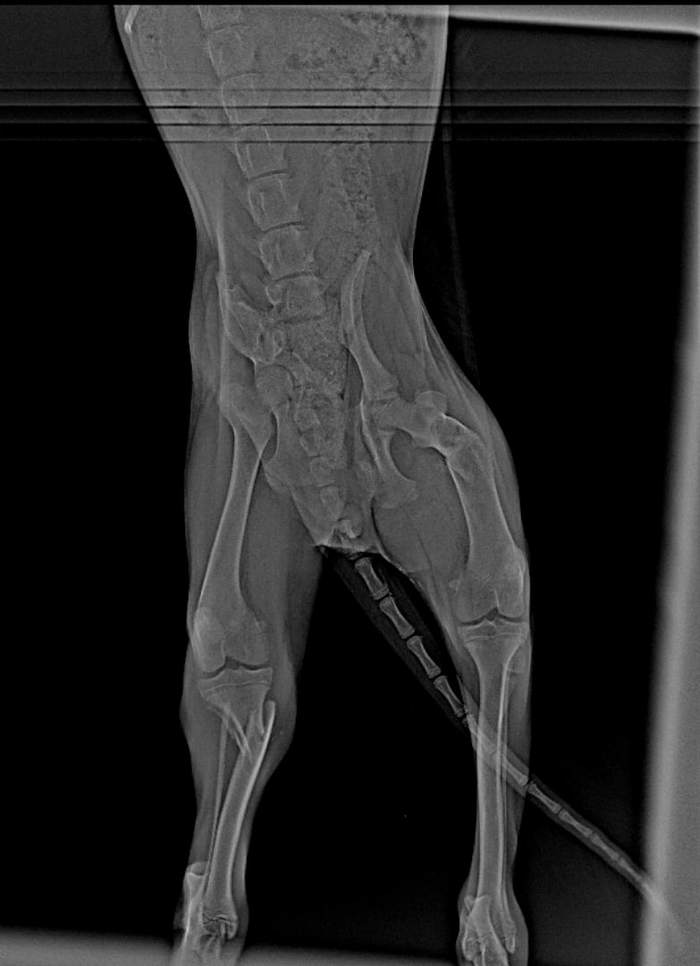

Есть шобака. Шобака классная. Но не везучая. Сидим мы в полночь с супругой дома, слышим удар,визг, проходит 5 секунд второй, визг уезжающей машины и тишина. Вы бегаем, видим это чудо. Спокойная, ласковая и почти что целая. Очень терпеливая при таких перелётах. Рентген показал оскольчатый перелом подвздошной кости справа, поперечный - слева, косой оскольчатый перелом бедра слева, оскольчатые переломы обеих костей голени. Еще шрам на пузе живописный такой. серьгу в ухе, которая свидетельствует либо о том, что она стерилизована, либо о том, что она неформалка.